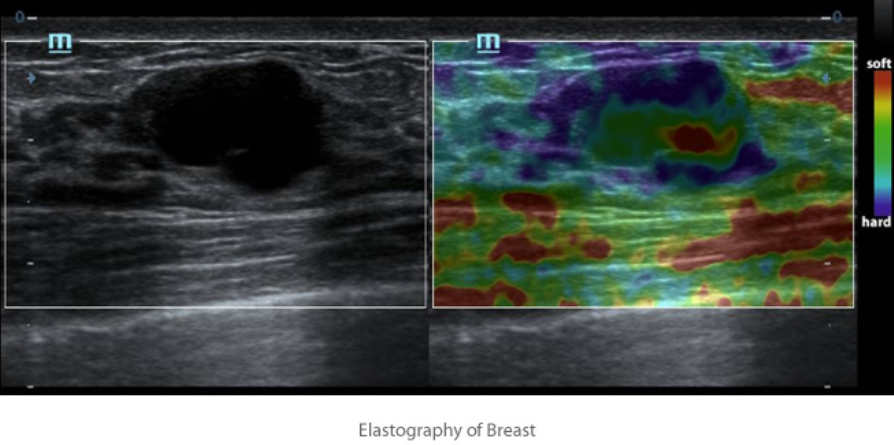

Natural Touch Elastography

Natural Touch Elastography? ?????? ?? ?? ??? ???? ??? ?? ??? ?? ???? ??????? ????

???? ???? ? ?? ??? ???? ?????.

- ? ?? ??(??)? ???.

- ??? ??? ? ???.